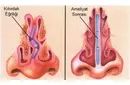

Fibröz kıkırdak, genellikle fibroblastlar tarafından üretilen kolajen tip I lifleri içerir. Bu lifler, kıkırdağın dayanıklılığını ve esnekliğini artıran bir ağ oluşturur. Fibröz Kıkırdak Türleri Fibröz kıkırdak, genel olarak iki ana türde bulunur:

Fibröz kıkırdak, genellikle eklemlerde, disklerde ve tendonlarda bulunur. Özellikle omurgada intervertebral disklerde ve bazı eklemlerde önemli bir rol oynar. Fibröz Kıkırdağın Fonksiyonları Fibröz kıkırdak, vücutta birçok önemli işlevi yerine getirir:

Fibröz kıkırdak, travma veya aşınma sonucu zarar görebilir. Bu tür durumlarda, kıkırdak onarım süreçleri yavaş ilerleyebilir ve genellikle cerrahi müdahale gerektirebilir. Fibröz Kıkırdak Hastalıkları Fibröz kıkırdak ile ilişkili bazı hastalıklar ve durumlar şunlardır: